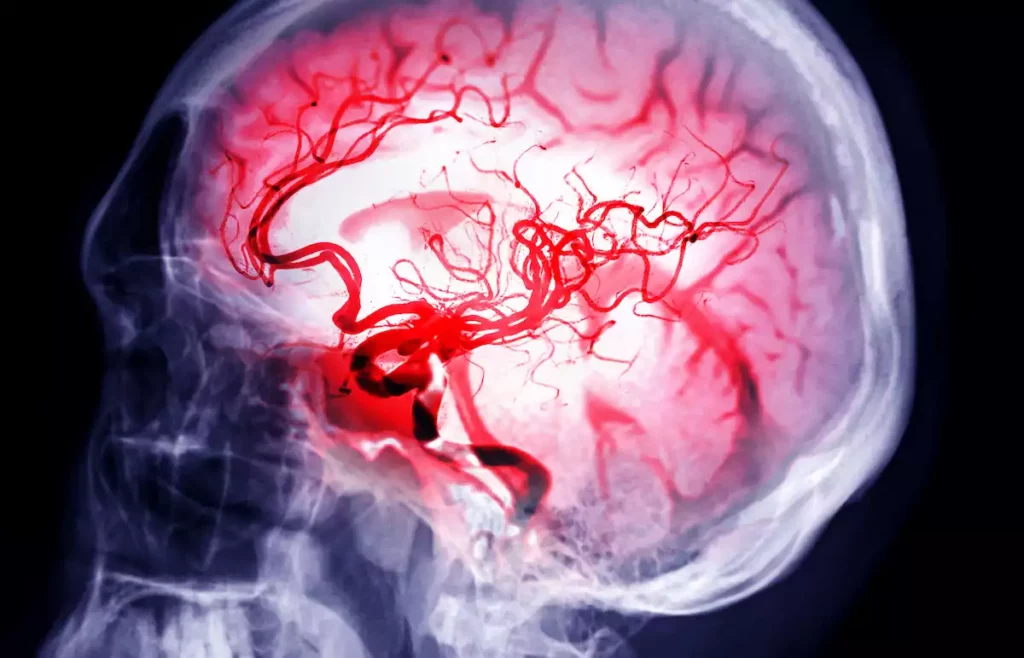

L’anévrysme définit un endroit de la paroi d’un vaisseau sanguin qui est affaibli. À cause de la pression sanguine, cette paroi crée une saillie, partie qui dépasse. La rupture d’anévrysme survient quand ce bout se remplie de sang éclate, provoquant une hémorragie. Certaines habitudes peuvent augmenter les risques.